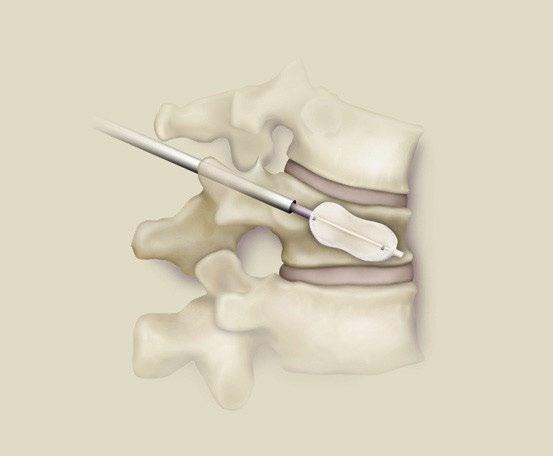

Local Therapy

Kasperk 2012 J Surg Oncol